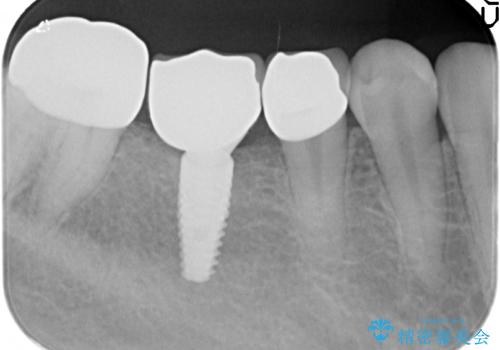

当院に初診来院時は左下の奥歯に重度歯周病が見られ、高度に骨吸収している状態でした。

抜歯後、高度に骨の吸収が生じたため骨の造成を行ったのちにインプラントを2本埋入、4ヶ月後に2次手術(歯ぐきの移植)を行いました。

骨・歯ぐきの環境を整えたのちに、最終的なかぶせものを作製していきます。

今回はジルコニアカスタムアバットメント、オールセラミックジルコニアクラウンで最終的な被せ物を作製しました。